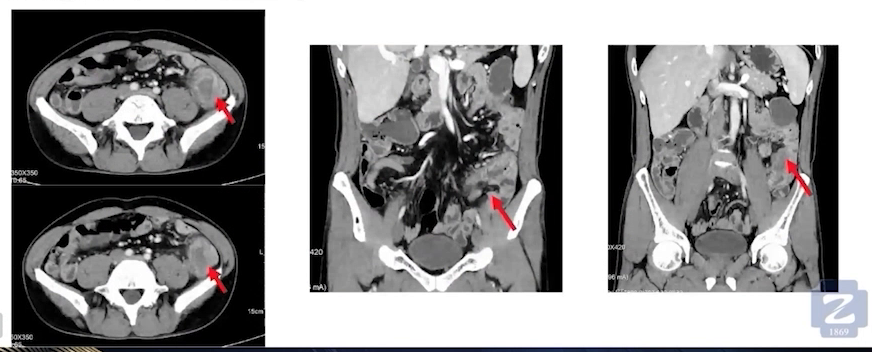

腹部CT:右半结肠癌术后改变。降结肠癌考虑,伴肠旁淋巴结转移,cT4aN1M0。

术前评估:经过3次术前新辅助免疫治疗后,2022年8月13日复查CT评估显示,左侧肿块及肠腔肿瘤明显缩小,梗阻症状明显缓解。8月16日肠镜复查,降结肠处仍可见肿块,肠腔缩窄,黏膜呈弥漫性增厚伴狭窄性改变,肠腔堵塞,进镜无法通过。